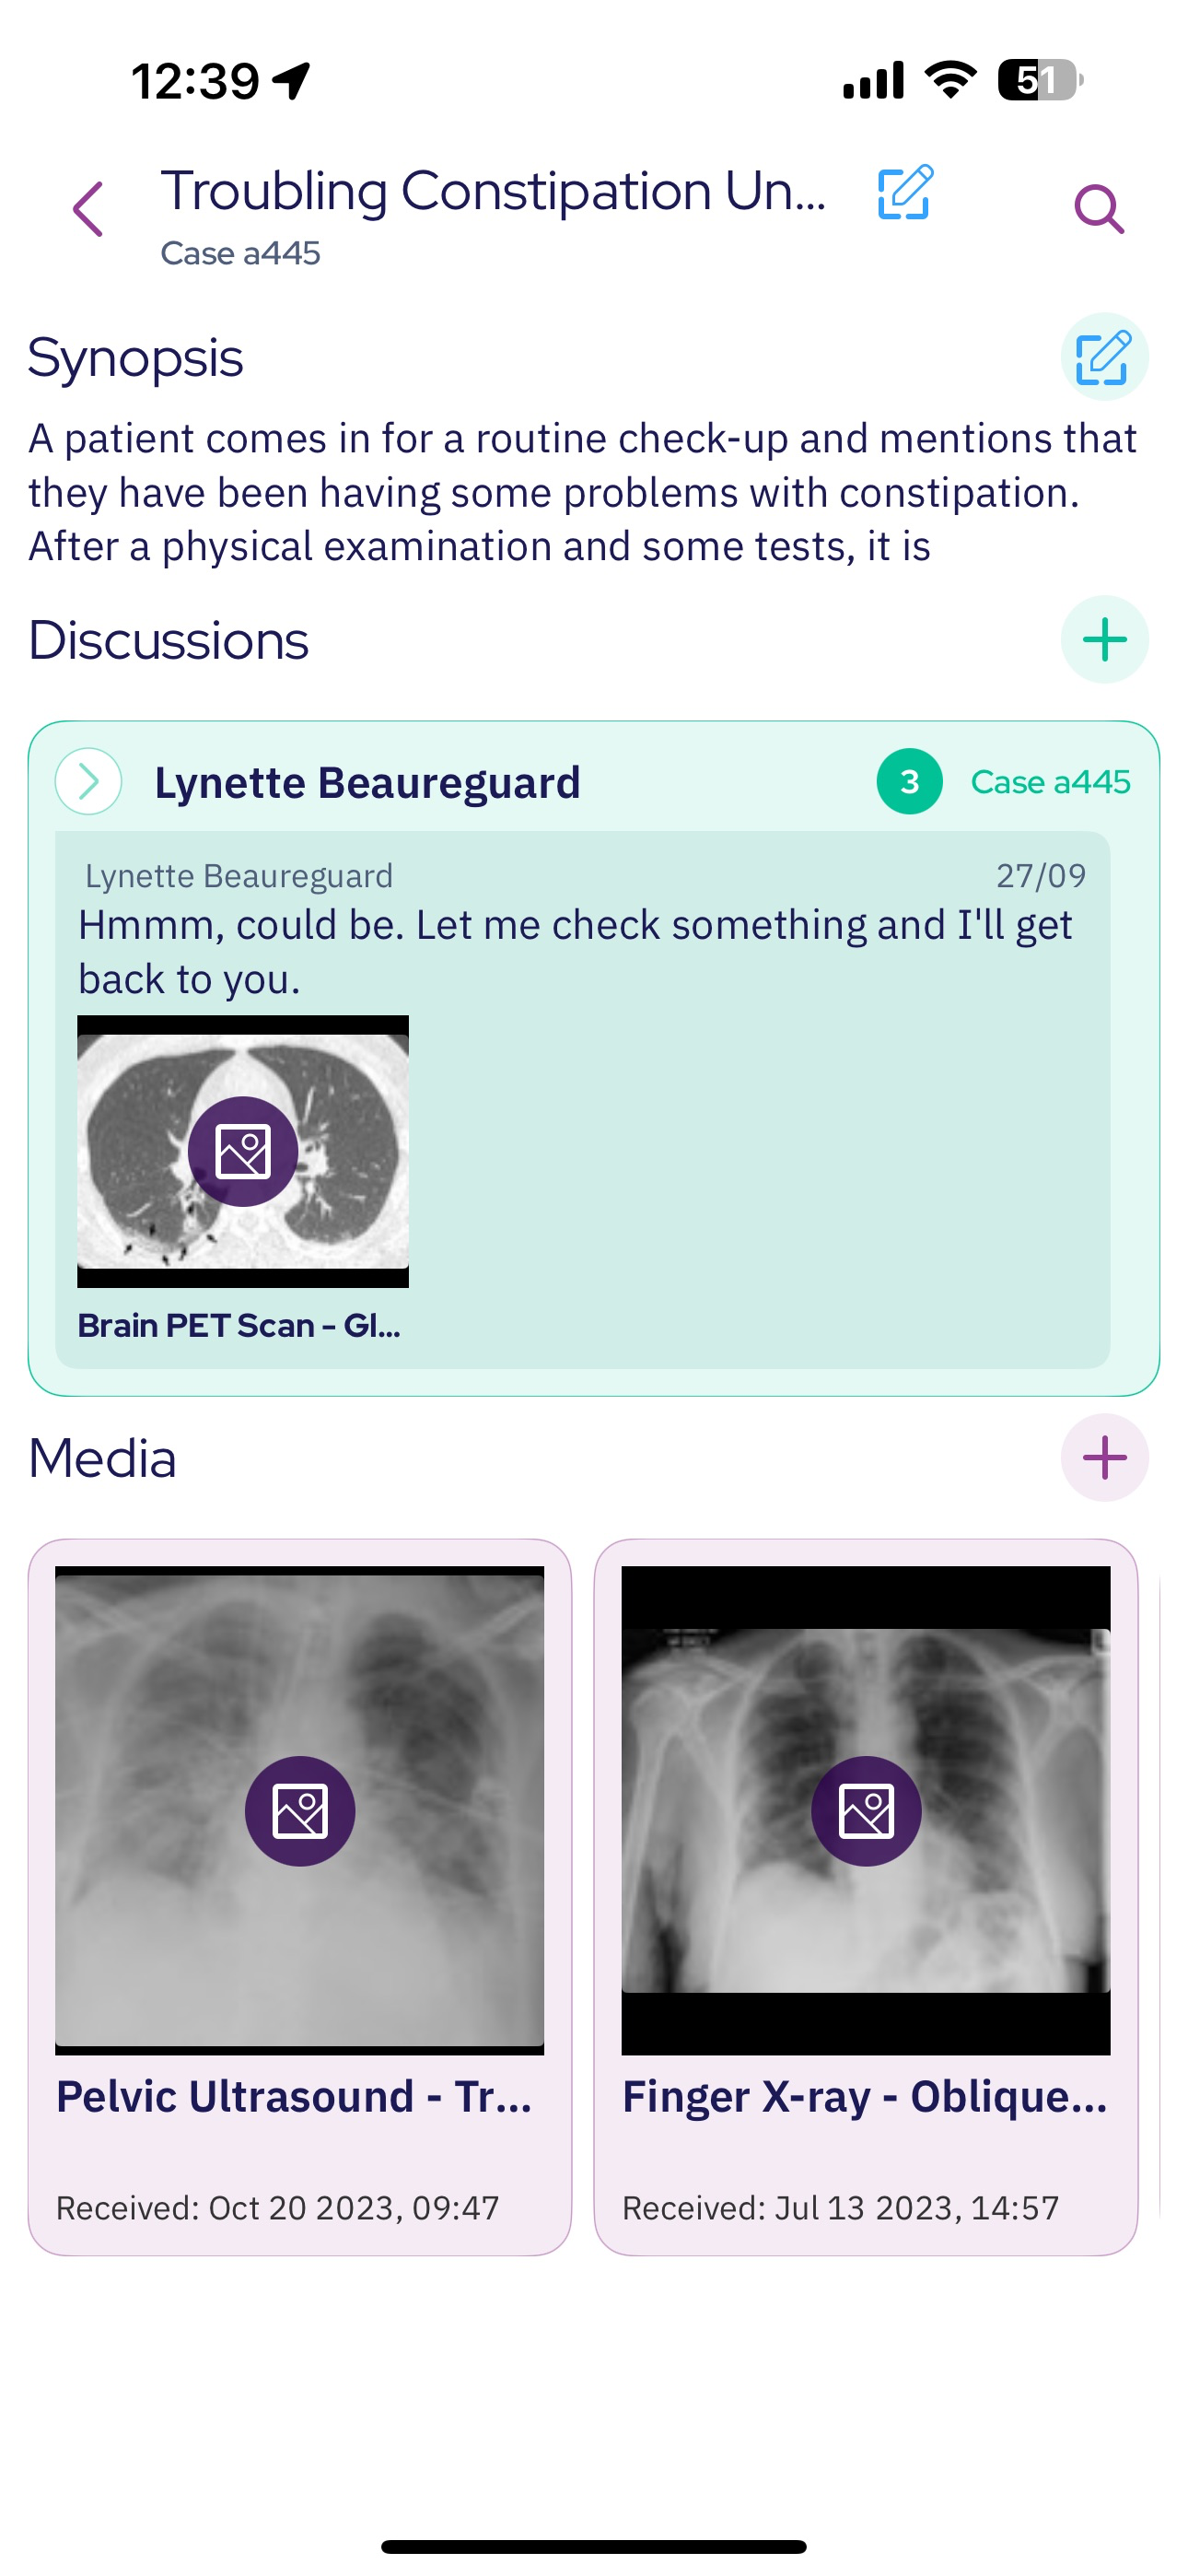

SeaGreen is a secure, open, free to use platform for healthcare professional to connect and collaborate. SeaGreen streamline consultation and collaboration such as AI powered capture mode that anonymize and a software virtual operating room.